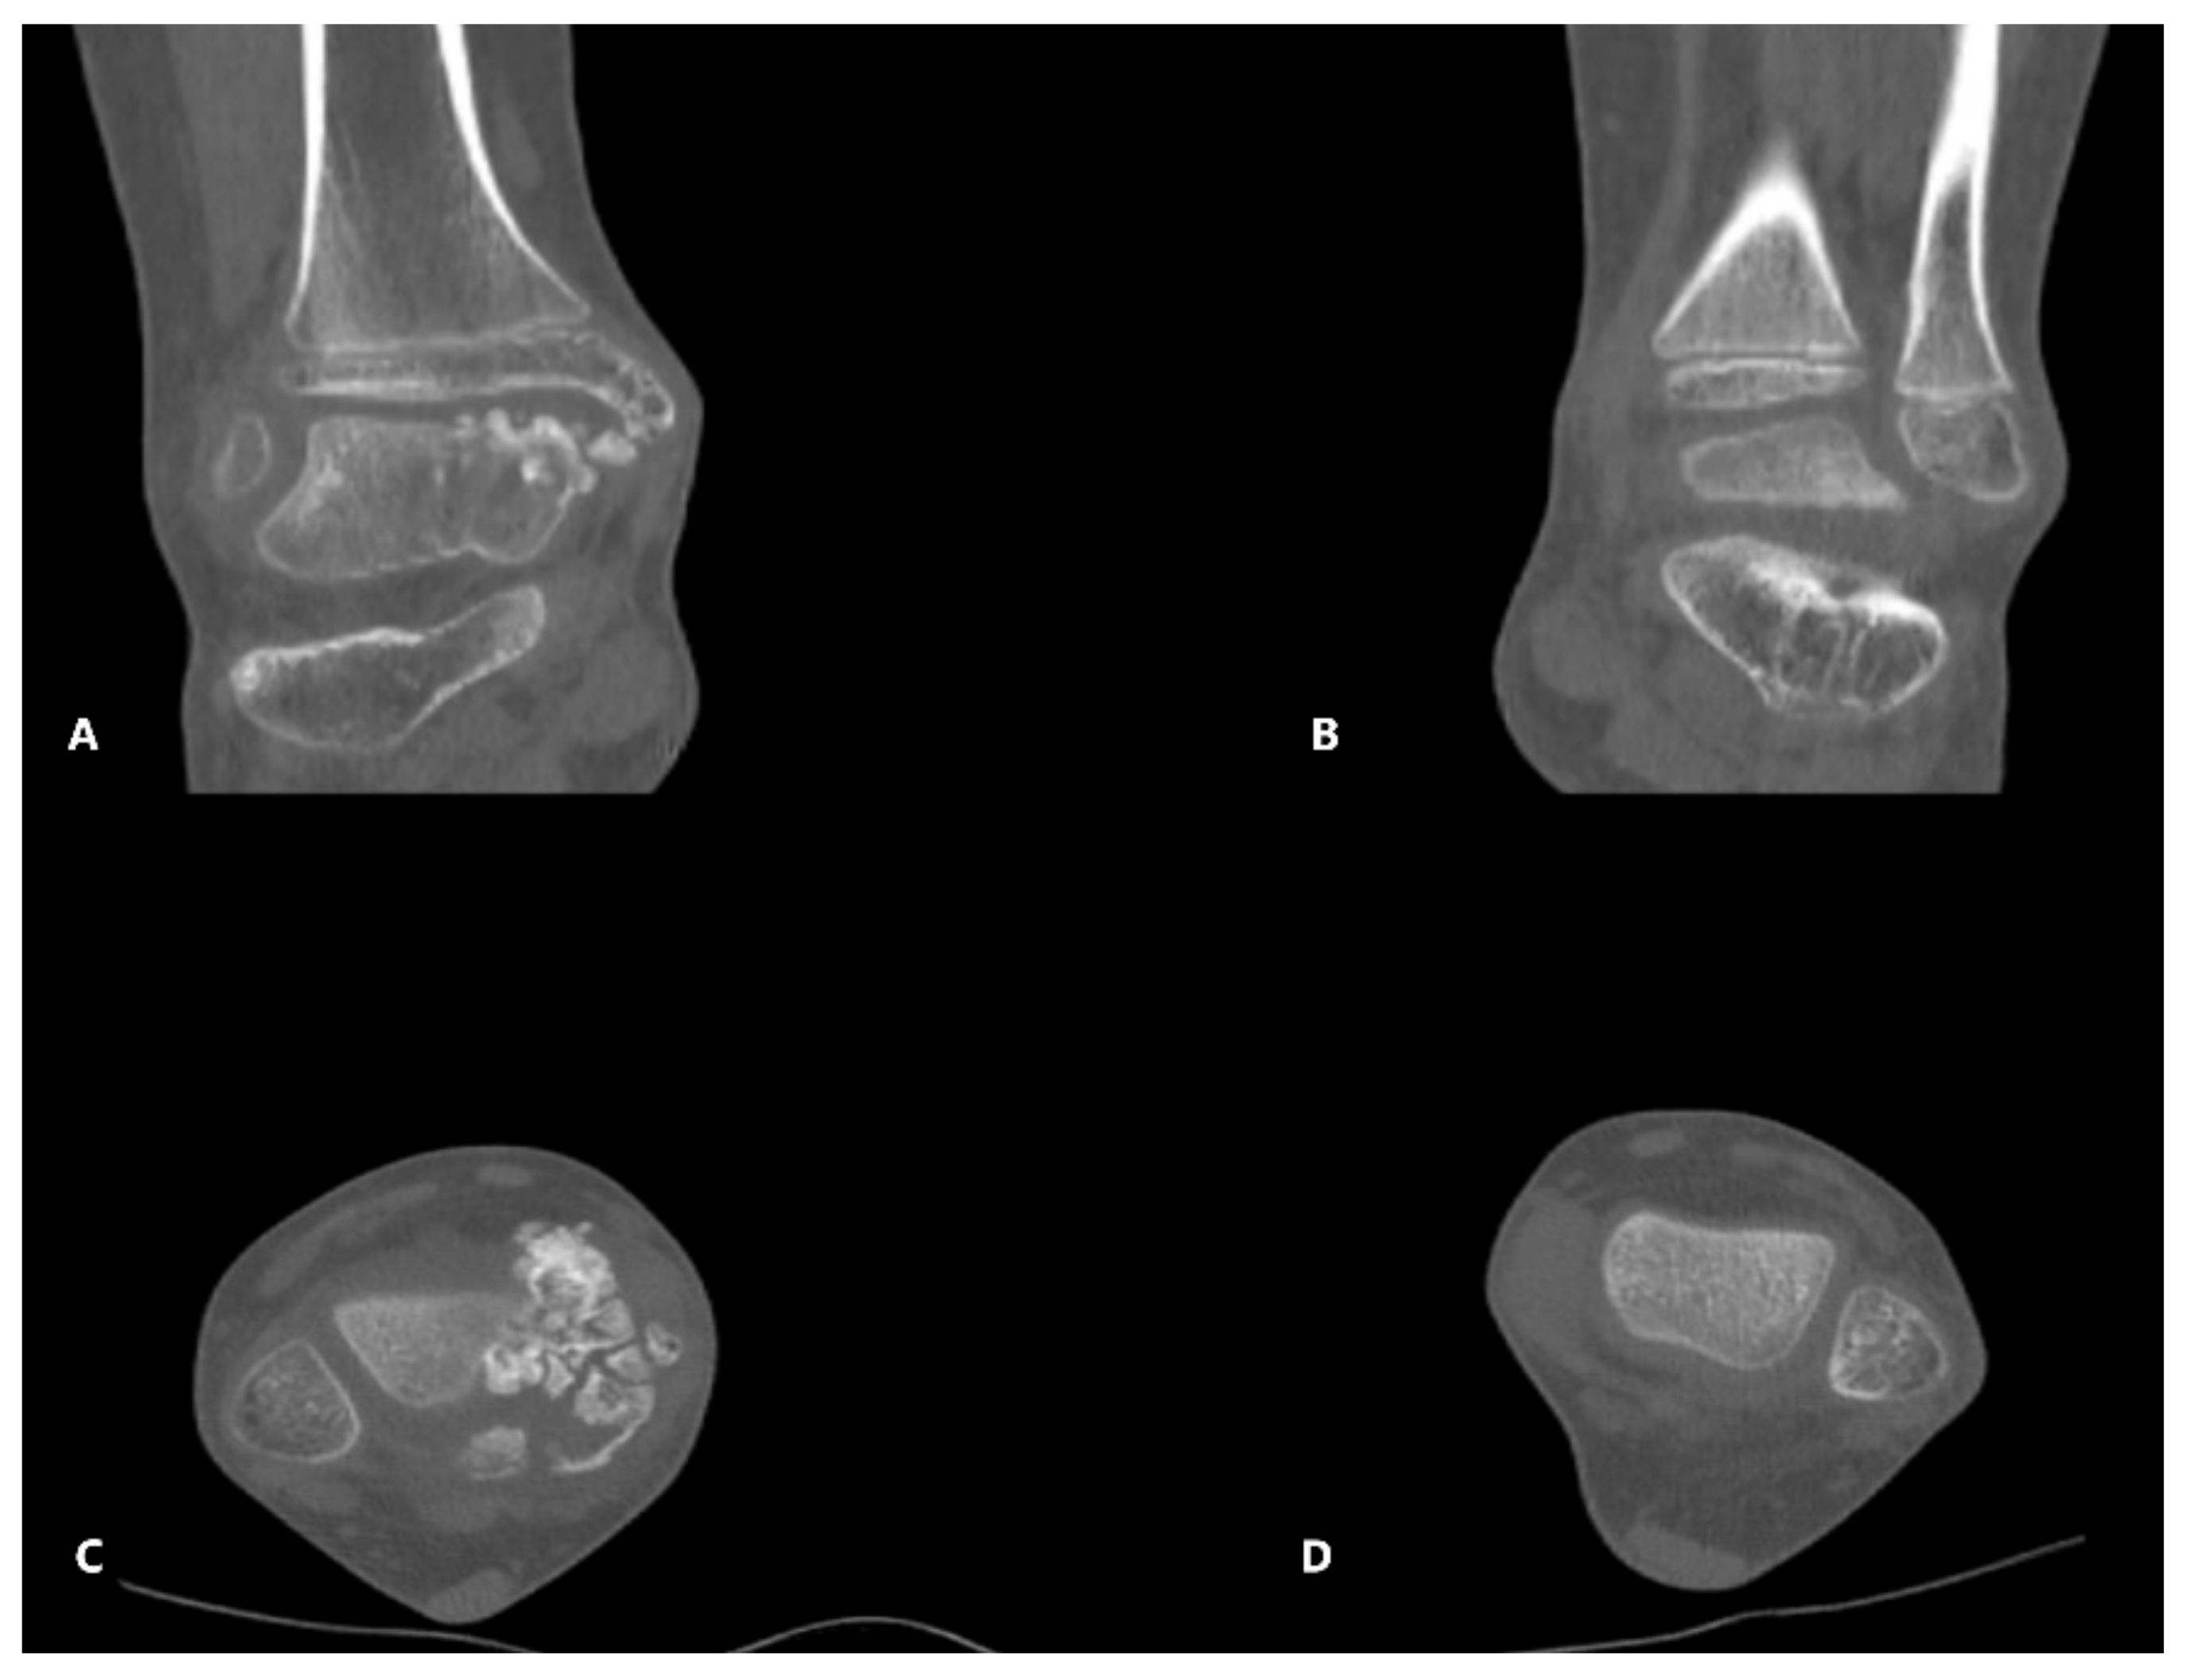

The patient underwent further investigations, such as CT scan and MRI of the right ankle (Figure 3, Figure 4 and Figure 5). The results suggested the presence of an osteochondral mass formed by multiple centers, well separated from the talus and the tibia. CT: computed tomography, MRI: magnetic resonance imaging

DEH disease is a complex disease, and because of its rarity, the diagnosis and treatment are often delayed. Strujis suggests that resection is justified anytime the pain or the deformity limits the range of motion and interferes with the normal activity of the patient [19]. In our first case, the main origin of the osteochondral centers was the talus. Complete resection of the pathologic tissue is essential to limit the chances of recurrence. Limited resection can be performed if there are more surgeries in plan for the future. The surgical resection was chosen after analyzing the clinical and radiological aspects of the tumoral mass. In this case, the 3D reconstruction of the CT scan images was extremely useful in the preoperative planning of the resection and in the parents understanding the necessity of a multiple step surgery. The decision to postpone the corrective osteotomy of the ankle was made based on the remaining growth potential of the patient.

Figure 4. (A) 3D CT reconstruction of both ankles- front view; (B) oblique view.